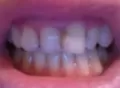

Мне 24 года, главная моя проблема — это выпирающие вперед верхние боковые резцы, а первые резцы с задней стороны полностью забломбированы на штифтах. Каким образом мне можно исправить кривизну передних верхних зубов? Носить брекеты желания нет.

Здравствуйте. Подскажите, возможно ли выровнять зубы (кривые только верхняя челюсть) без брекетов? У меня торчат 2 зуба вверху. Можно ли их сточить и наростить искуственные?